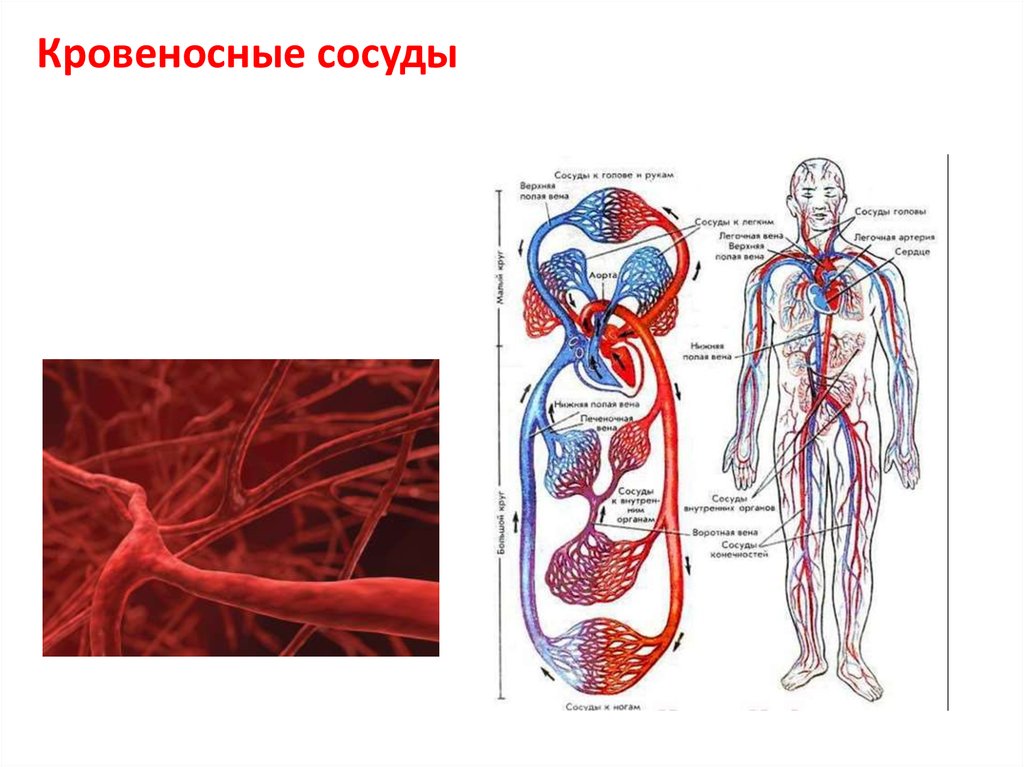

Кровеносная система человека: структура и функции

Раздел: Идеи и советы